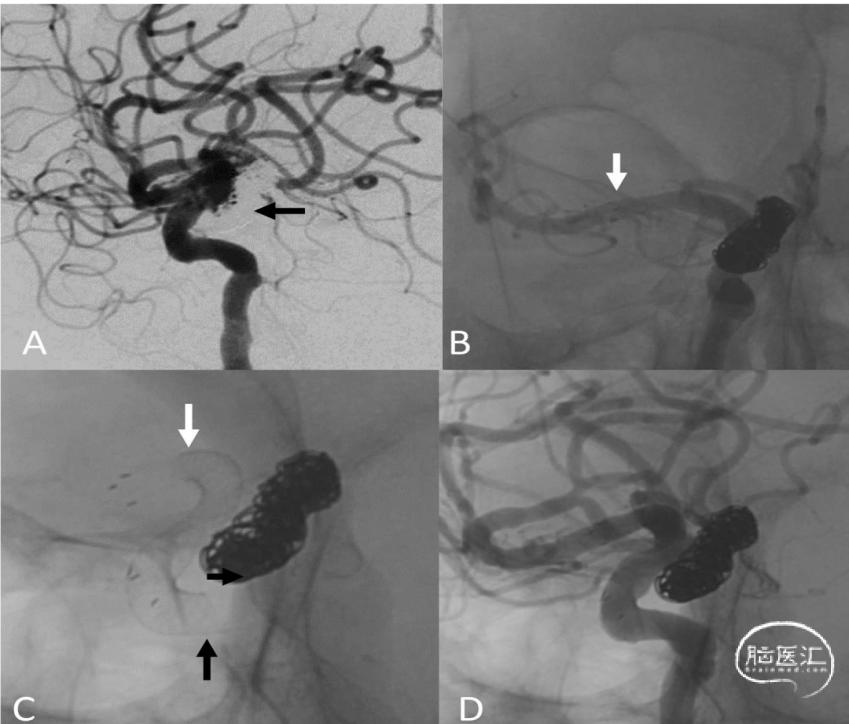

图1:一名38岁女性患者在接受支架辅助弹簧圈栓塞术治疗1个月后,出现Hunt-Hess 1级蛛网膜下腔出血(SAH)。

A. 右侧颈内动脉造影,侧位视图,显示床突上段复发的水泡样动脉瘤(箭头所示)。

B. 透视图像,斜位视图,显示弹簧圈紧密填塞,但Enterprise支架两端贴壁不良(箭头所示)。随后,成功植入一枚Pipeline栓塞装置(PED;4.0×20mm,美敦力公司),覆盖了先前支架的近端和远端。

C. 未减影图像,侧位视图,显示Enterprise支架两端贴壁良好(箭头所示)。

D. 6个月随访时的数字减影血管造影,右侧颈内动脉侧位视图,显示动脉瘤完全闭塞。